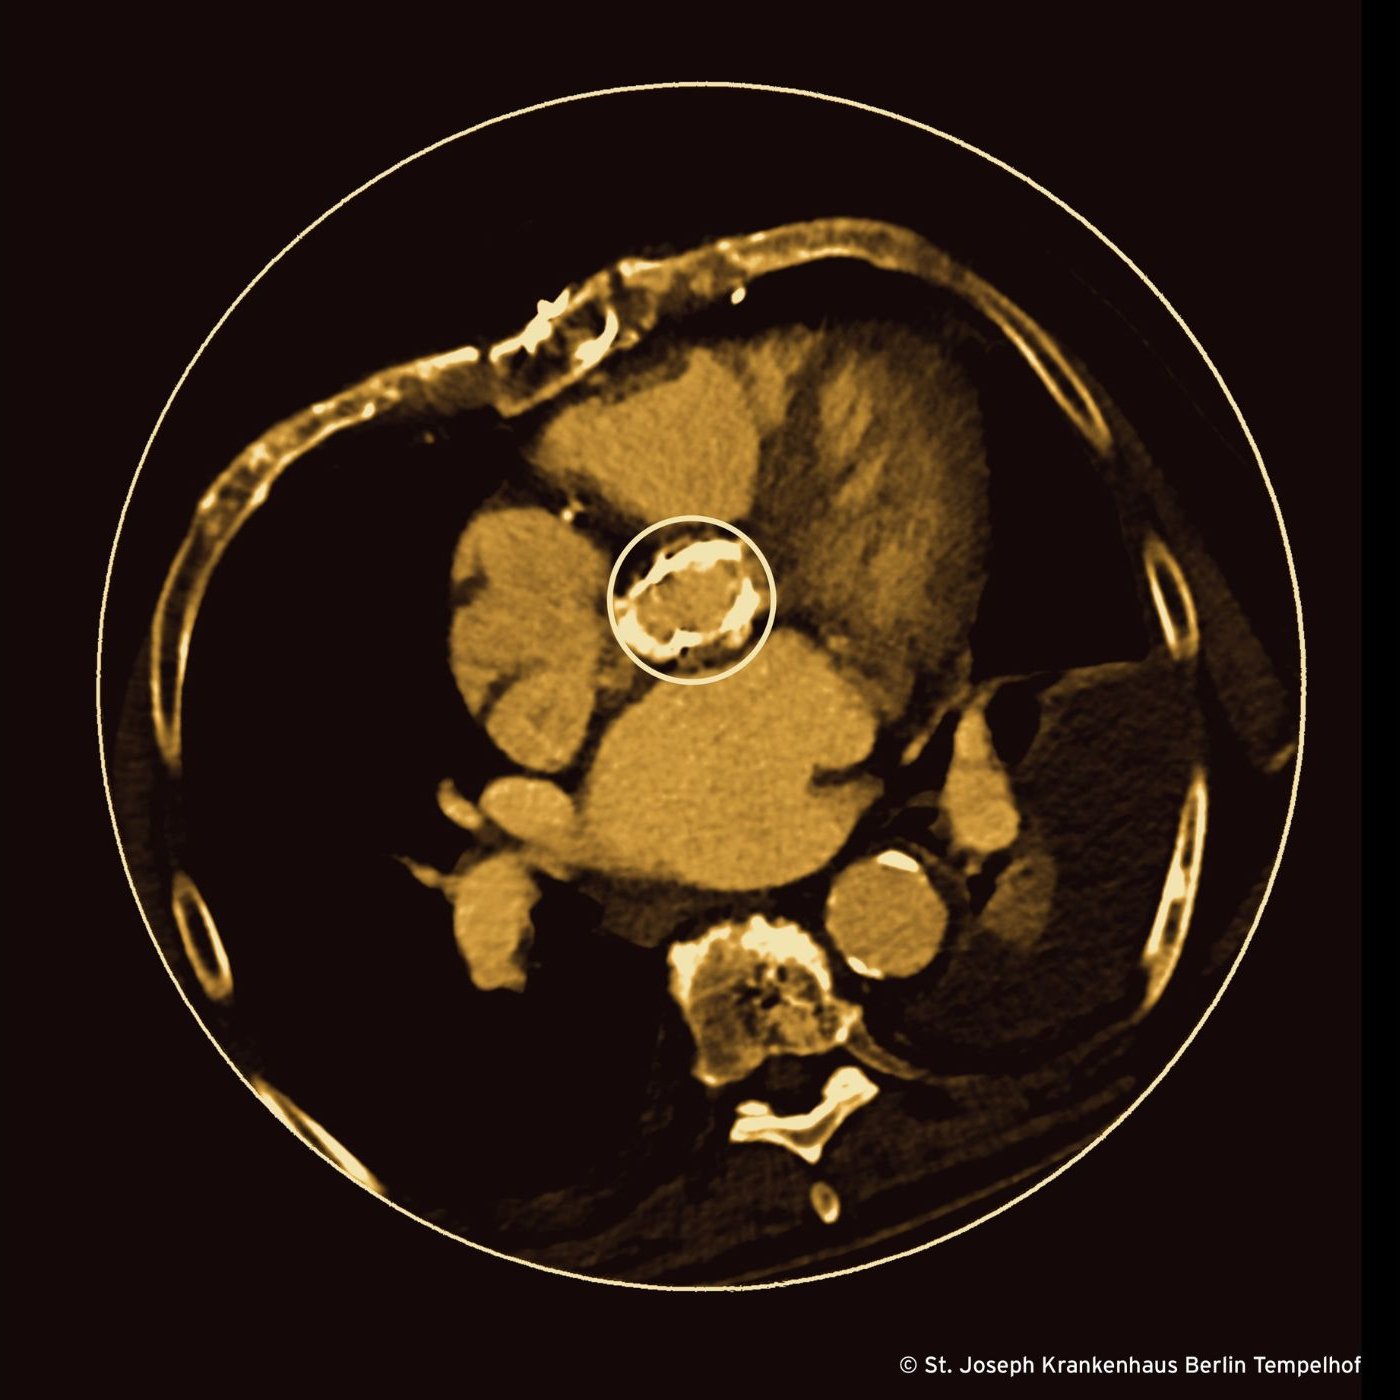

Eine Klappe ist wie eine Dornenkrone im Fleisch des Herzens. Ihre Stacheln bohren sich durch die Gleitschicht des Gefäßsystems, sie verursachen Verletzungen, die die Gerinnungskaskade aktivieren. Am Rande jeder Klappe, dort wo die Strömung turbulent ist, können sich am traumatisierten Endothel sterile Vegetationen aus Fibrin und Blutplättchen bilden, welche wiederum ein gefundenes Fressen für temporär im Blutstrom treibende Bakterien sind. Warum also ausgerechnet Enterokokken, Bakterien, denen man eigentlich nicht so viel zutraut?